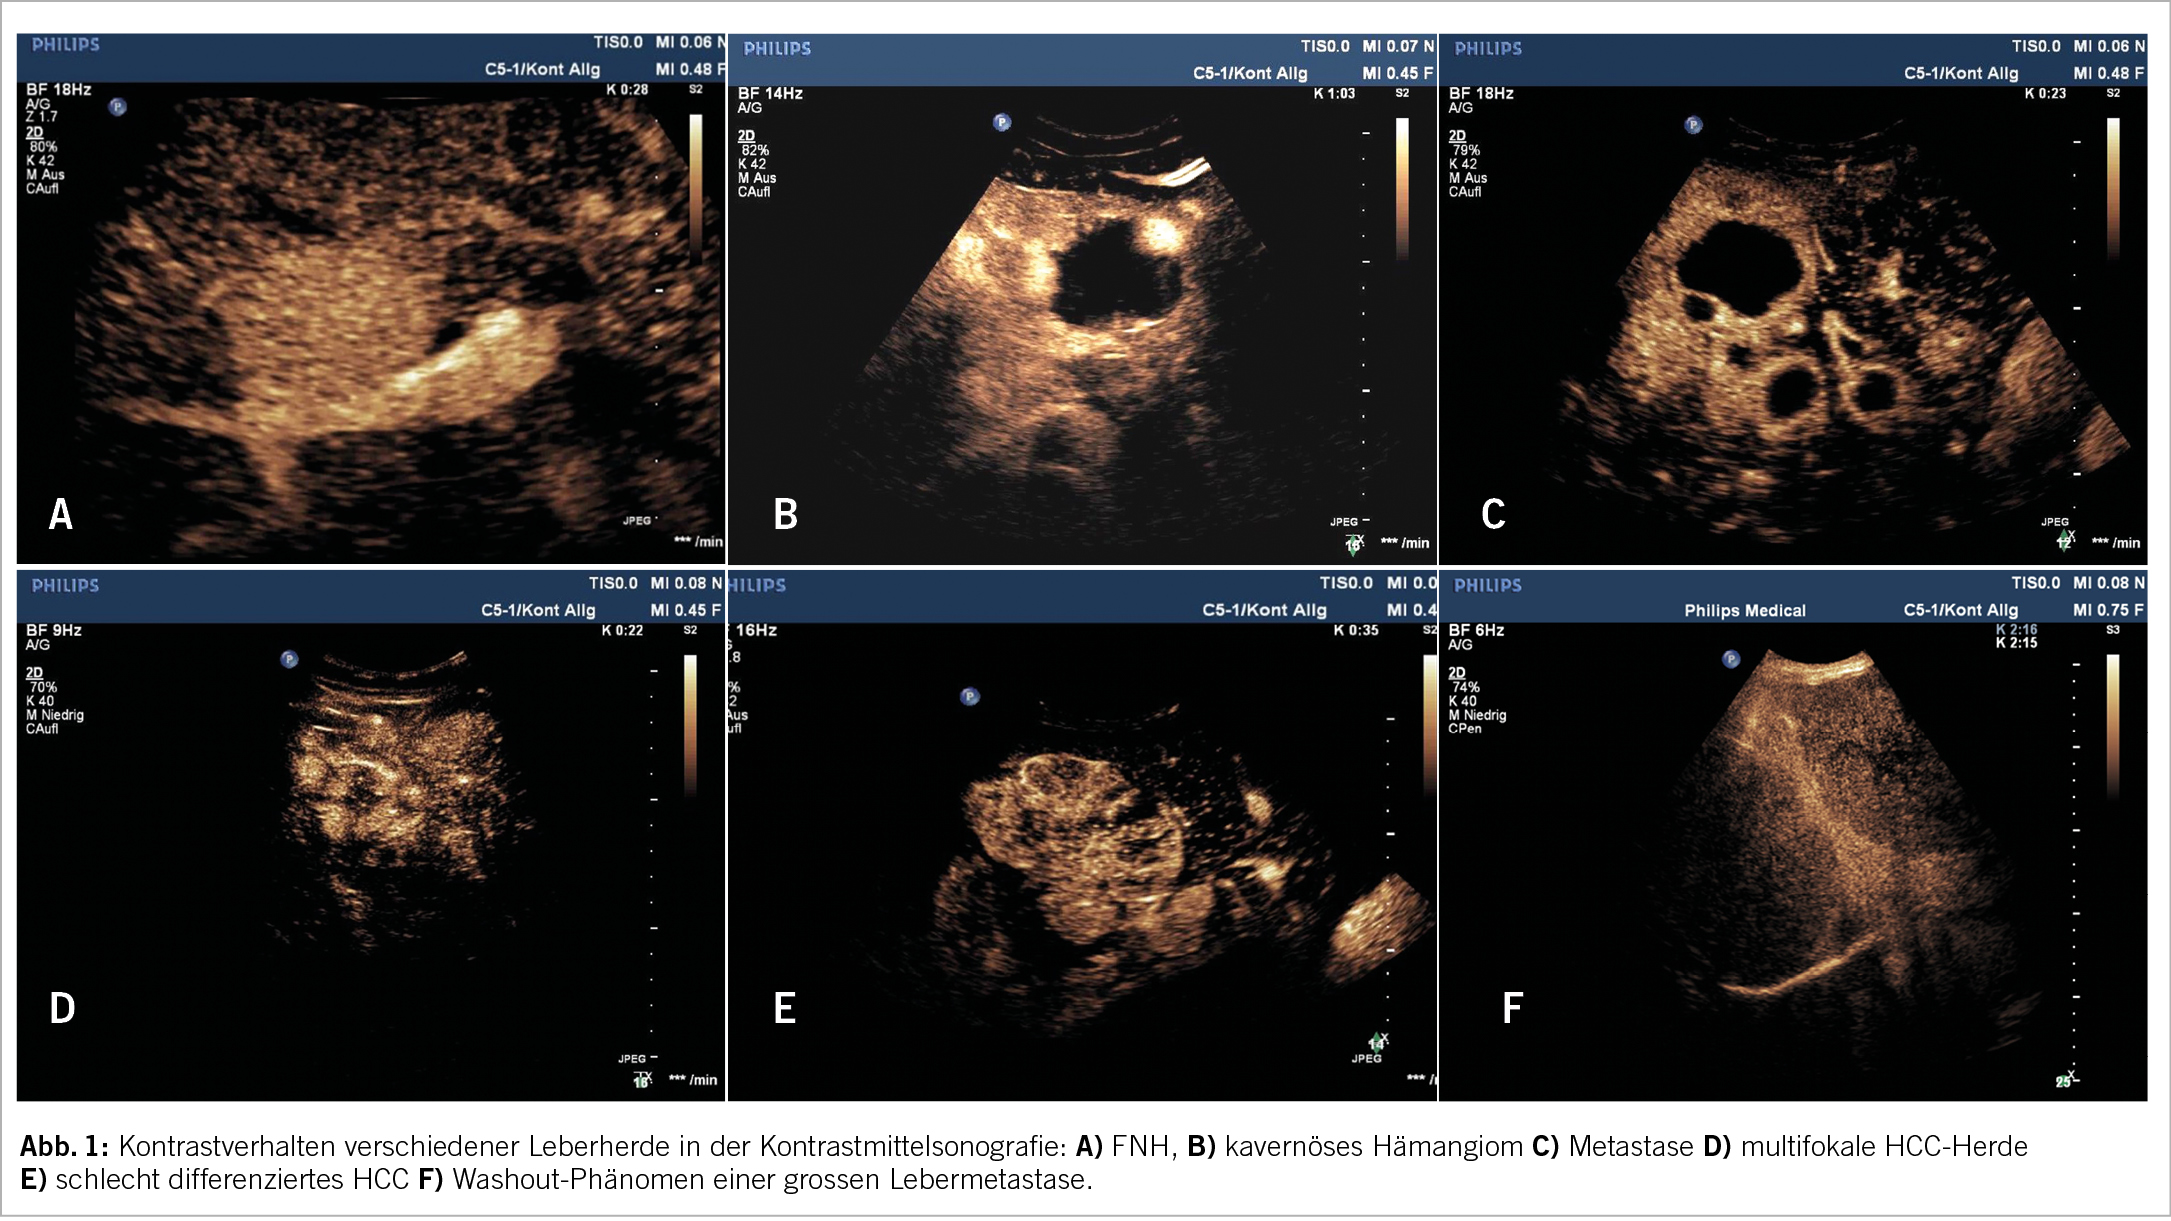

Hierbei wird nach intravenöser Applikation eines Kontrastverstärkers dessen Verteilung innerhalb der Läsion sowie im umgebenden Gewebe in Echtzeit dargestellt (real-time-Untersuchung). Die Beurteilung des arteriellen Vaskularisierungsmusters sowie des KM-Verhaltens im Laufe weniger Minuten nach Applikation ermöglicht in vielen Fällen eine Artdiagnose der Läsion sowie mit hoher Sicherheit eine Unterscheidung zwischen benignen und malignen Läsionen. Letztere gelingt insbesondere bei Leberraumforderungen deshalb, weil maligne Läsionen nicht über die duale Perfusion gesunden Lebergewebes verfügen- also nicht sowohl arteriell wie auch portalvenös versorgt werden. Das für den Ultraschall verwendete Kontrastmittel besteht aus Mikroblasen mit einem Lipidmantel, die nach der Untersuchung abgeatmet bzw. verstoffwechselt werden. Das Nebenwirkungsprofil ist extrem günstig, lediglich sehr seltene allergische Reaktionen sind beschrieben. Nachteil der Methode ist die Abhängigkeit von Erfahrung des Untersuchers und den Untersuchungsbedingungen.

Hämangiome sind die häufigsten gutartigen soliden Lebertumore. In Autopsien sind sie in bis zu 20% gesunder Lebern zu finden (5). In der überwiegenden Zahl der Fälle sind die Läsionen asymptomatisch, Ausnahmen können die > 10 cm messenden Riesenhämangiome darstellen. Grössenänderungen im Verlauf sind möglich. Unterschieden wird zwischen kavernösen Hämangiomen mit langsamem Blutfluss und meist im Verlauf vorhandenen Teilthrombosierungen und meist kleineren Läsionen mit hohem Blutfluss. Das klassische sonografische Bild des kavernösen Hämangioms entspricht einer < 3cm grossen, weitgehend homogenen, echoreicheren Läsion, die manchmal ein zuführendes Gefäss, jedoch in der Regel keine Binnenperfusion im Farbdoppler erkennen lässt. Auch hier ist bei typischem Erscheinungsbild die Diagnose durch B- Bild und Duplexsonografie möglich. Eine zusätzliche Kontrastbildgebung ist meist notwendig, wenn Hämangiome mit hohem Blutfluss oder Hämangiome in Fettlebern als echoarme Herdbefunde imponieren oder infolge intratumoraler Teilthrombosen und Sklerosierungen echoinhomogenere Gebilde vorliegen. Beinhaltet die Vorgeschichte des Patienten eine Tumor- oder chronische Lebererkrankung, empfehlen die aktuellen Leitlinien auch im Falle typischer sonografischer Befunde eine kontrastmittelgestützte Bildgebung (5). Hämangiome zeigen in allen bildgebenden Verfahren typische Kontrastphänomene: ein peripher- noduläres Enhancement und im Verlauf eine nach zentral zunehmende KM-Anflutung, auch als Irisblendenphänomen bezeichnet. In seltenen Fällen können vor allem sehr grosse Hämangiome komplexere KM- Bilder erzeugen, die eine Zuordnung schwierig machen.

Fokale noduläre Hyperplasie

Die FNH macht ca. 8% der gutartigen Lebertumore aus und wird gehäuft bei Frauen jungen und mittleren Alters gefunden. Die Läsion besteht histopathologisch aus einer Hyperplasie von Lebergewebe als Antwort auf gesteigerten lokalen arteriellen Blutfluss infolge einer Gefässmalformation (9). Sie tritt in bis zu 30% multifokal auf. Im B- Bild stellt sich die FNH als zumeist isoechogene Läsion mit feinen fibroseartigen Strangmustern und einer zentralen echoreicheren Narbe dar. Bei richtiger Duplexeinstellung lässt sich oft bereits ein bei der typischen Form zentral, bei atypischen Formen peripher liegendes stern- oder radspeichenartig sich aufzweigendes arterielles Gefäss erkennen. Im PW- Doppler weist es typischerweise einen niedrigen Resistenzindex mit Werten bis zu 0,2 auf (10). Die Erstdiagnose sollte eine kontrastgestützte Bildgebung umfassen. Sowohl Kontrastmittelsonografie als auch MRT mit hepatobiliären Kontrastmitteln besitzen eine sehr hohe diagnostische Aussagekraft. Die diagnostische Genauigkeit der Kontrastmittelsonografie betrug in einer aktuellen Studie knapp 99% bei einer Sensitivität von 85% und einer Spezifität von 99,5% (11). Typisch für die FNH sind das rasche arterielle Anfluten mit zentrifugaler Ausbreitung, die Radspeichenstruktur der Gefässe mit zentraler Narbe und das Isoenhancement in den späten Phasen. In seltenen Fällen diagnostischer Unsicherheit, insbesondere wenn die Abgrenzung vom hochdifferenzierten HCC schwerfällt, kann zunächst die Kombination einer MRT mit einer Kontrastmittelsonografie zusätzliche Sicherheit bringen (5), ansonsten können eine bioptische Klärung oder alternativ bildgebende Verlaufskontrollen im Abstand weniger Monate erwogen werden. Die FNH ist durch einen komplikationsarmen Verlauf gekennzeichnet, wenn auch in manchen Fällen ein Grössenwachstum beobachtet werden kann. Hämorrhagische Ereignisse sind extrem selten, eine maligne Entartung tritt nicht auf. Entgegen früherer Annahmen muss die Einnahme von Kontrazeptiva nicht beendet werden, dann sind jedoch anfängliche sonografische Verlaufskontrollen in Abständen von 1-2 Jahren sinnvoll.

Metastasen

Das HCC tritt in der überwiegenden Zahl der Fälle in einer zirrhotischen Leber auf. Ist keine Zirrhose vorhanden, sind in Europa die chronischen Hepatitiden die häufigsten Präkanzerosen. Insgesamt liegt über 90% der HCCs eine chronische Erkrankung zugrunde. Die differenzialdiagnostische Herausforderung liegt in der Abgrenzung von Regeneraten und dysplastischen Knoten in der Zirrhoseleber. Im konventionellen Ultraschall sind uni- oder multifokale, iso-, hyper- und hypoechogene Erscheinungsformen möglich. Jeder sonografisch entdeckte Herdbefund in einer Zirrhose muss wegen des Verdachts auf ein HCC einem durch die aktuellen Leitlinien festgelegten diagnostischen Algorithmus zugeführt werden (14,15). HCCs durchlaufen einen Prozess zunehmender Entdifferenzierung, dem eine Zunahme der arteriellen Vaskularisation entspricht. Die Leitlinien betonen den Stellenwert der kontrastgestützten Bildgebung, in der das HCC eine früharterielle Hyperperfusion und ein verzögertes Washout aufweist. Der Nachweis dieser typischen Kontrastmittelbefunde gelingt in CT, MRT und Kontrastultraschall mit vergleichbarer diagnostischer Genauigkeit (13) und erlaubt ohne weitere Diagnostik die Diagnose eines HCC (Abb. 2). Probleme bereiten in allen bildgebenden Verfahren kleinere Tumore < 2 cm, da diese nur in ca. 50% die charakteristischen Kontrastmittelphänomene aufweisen (16). In solchen Fällen wird, falls technisch möglich, primär eine Biopsie angestrebt. Herdbefunde < 1 cm Grösse in einer Zirrhose werden in der Regel in 6-monatigen Abständen kontrolliert.